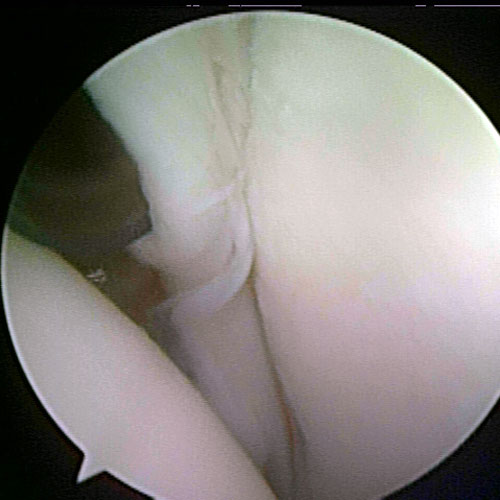

shoulder arthritis picture

Shoulder arthritis arthroscopic image